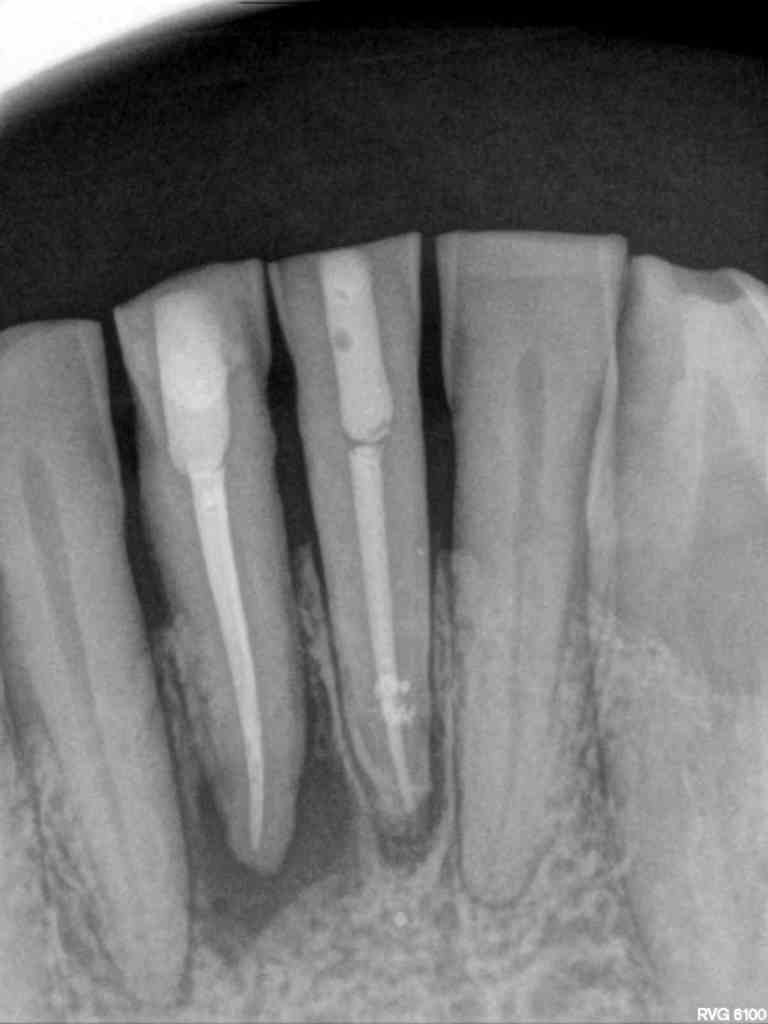

El paciente acude a la consulta en 2022 con sintomatología compatible con necrosis pulpar en el diente 3.1. Tras la confirmación diagnóstica, se realiza el tratamiento de conductos. Un año después, el diente 4.1 presenta un cuadro clínico similar, asociado a la sobrecarga funcional derivada del bruxismo. Se diagnostica necrosis pulpar y se procede igualmente a realizar tratamiento endodóntico. En 2025, el paciente acude con la presencia de una fístula vestibular a nivel del 4.1. Tras la evaluación clínica y radiográfica, se concluye la existencia de una fractura radicular vertical, lo que compromete el pronóstico del diente (Figuras 1-6).